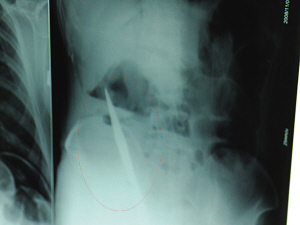

X光片上,尖刀清晰可見。

從男子體內(nèi)取出的尖刀足足有19厘米長(zhǎng)。

6日上午,記者在徐州礦務(wù)集團(tuán)總醫(yī)院重癥監(jiān)護(hù)室見到了這名男子,目前他雖然已經(jīng)恢復(fù)了意識(shí),但還不能開口說(shuō)話,需要呼吸機(jī)輔助呼吸。據(jù)醫(yī)生介紹,4日中午12時(shí)左右,這名男子因服毒輕生被緊急送到醫(yī)院進(jìn)行搶救,之前,這名男子已經(jīng)在當(dāng)?shù)剜l(xiāng)鎮(zhèn)醫(yī)院進(jìn)行了近20小時(shí)的治療,但效果不佳!安∪吮晦D(zhuǎn)院到礦總院時(shí)已神志不清,血壓極低,處于休克狀態(tài)!本茸o(hù)人員給男子洗胃、初步處理以后,發(fā)現(xiàn)男子呼吸急促,于是趕緊給他拍片檢查。結(jié)果讓所有的醫(yī)生大吃一驚,竟有一把尖狀異物橫在該男子腹腔內(nèi)!當(dāng)天下午5時(shí)30分,輕生男子被推上了手術(shù)臺(tái)。經(jīng)過(guò)40多分鐘的手術(shù),該男子腹腔被打開,手術(shù)醫(yī)生發(fā)現(xiàn),男子體內(nèi)的金屬狀異物竟然是一把長(zhǎng)19厘米的尖刀!